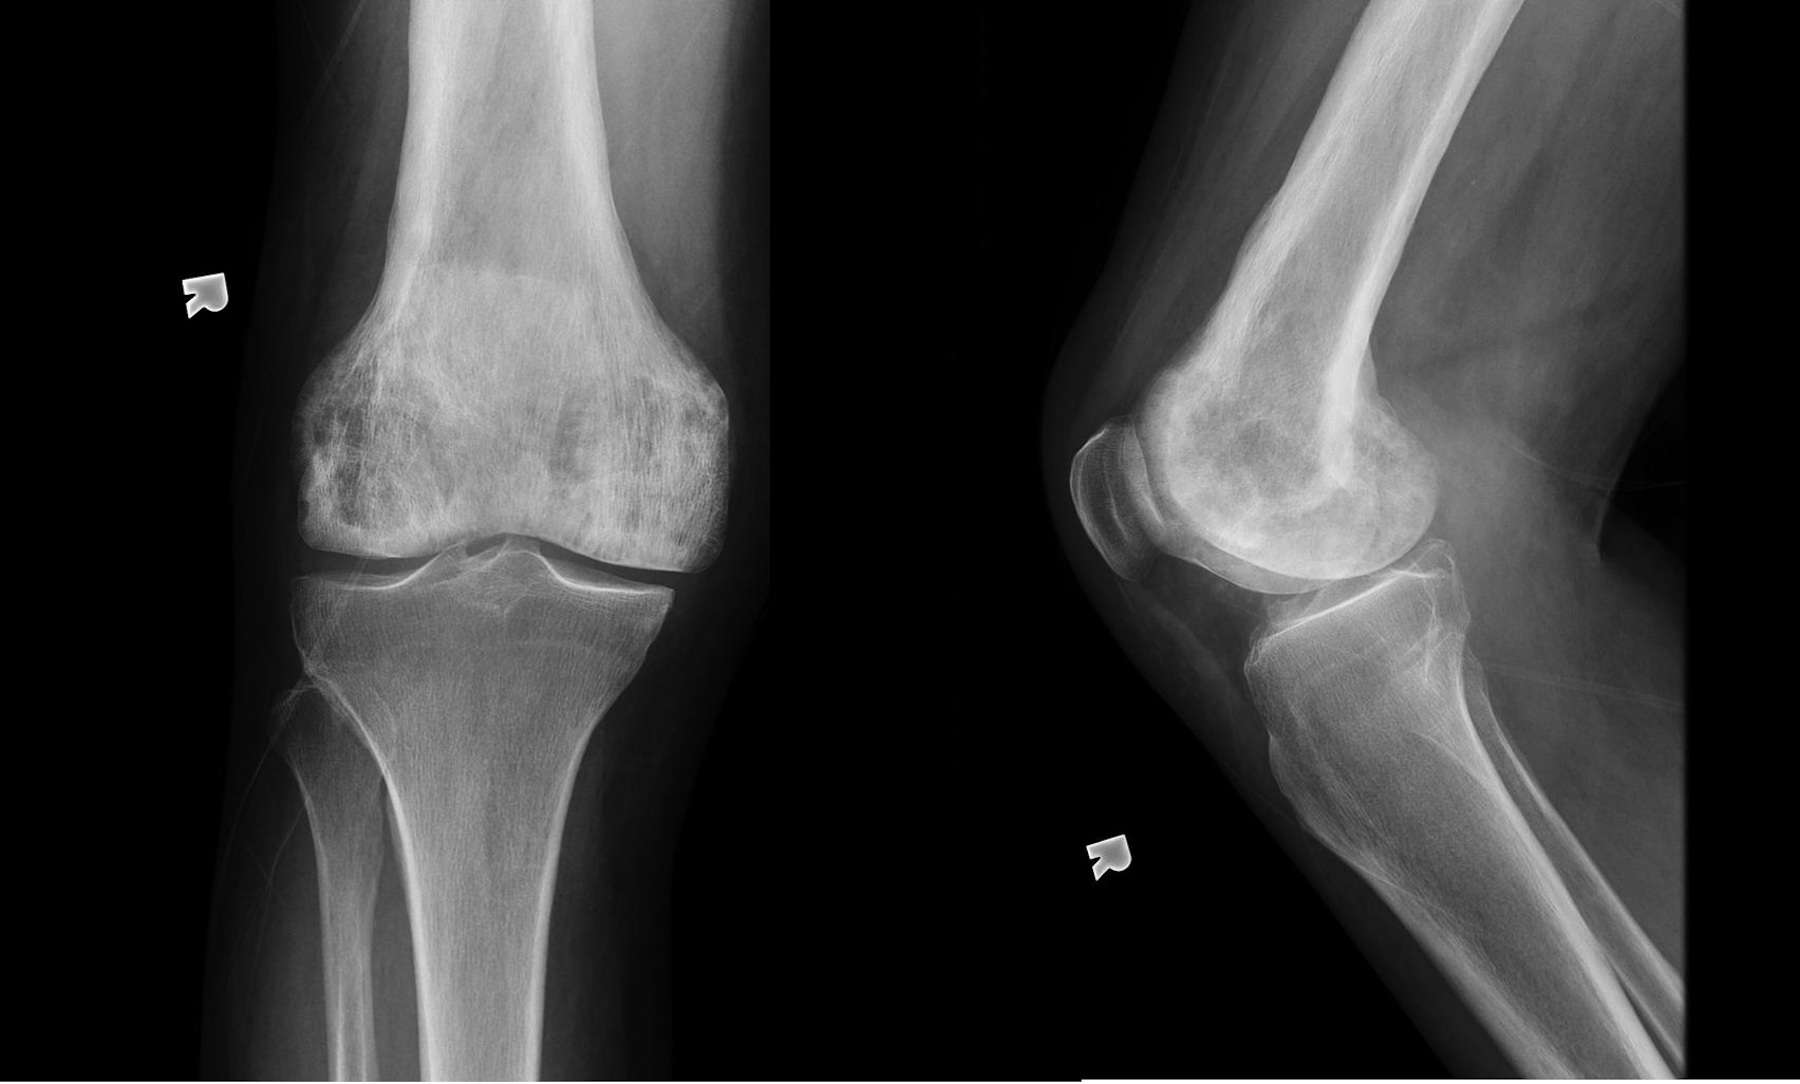

La maladie de Paget aboutit à des douleurs des hanches ou du dos avec déformation des os longs.